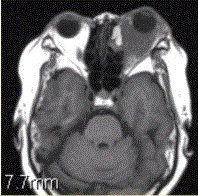

问题 患者女,64岁,左眼突出5年余。查体左眼球前突6mm,眼球运动自如,眼底无异常,下睑扪及边界不清、质软的肿块,视力正常,MR表现如下图。 经抗生素及激素治疗后好转,则诊断支持

选项 A.炎性假瘤 B.眼型Grave病 C.黑色素瘤 D.转移瘤 E.眼眶海绵状血管瘤 F.弥漫型淋巴管瘤

答案 A